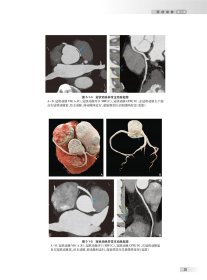

• 中华影像鉴别诊断学——心血管分册

内容摘要

本书简要描述该征象的病理基础,要从读者便于理解影像征象的角度寻找其病理支撑。描述该征

象在各种影像方法上的主要表现。主要列出要鉴别的疾病。此内容结合作者经验宏观的介绍此征象,给读者清晰的思路,形成良好的阅片和分析习惯。

对不同心脏疾病诊断的价值和特异性等。对相关疾病列出其特点和鉴别点。为心内、心外科室医生提供疾病诊断的参考书,提高医学影像的诊断和鉴别诊断水平。